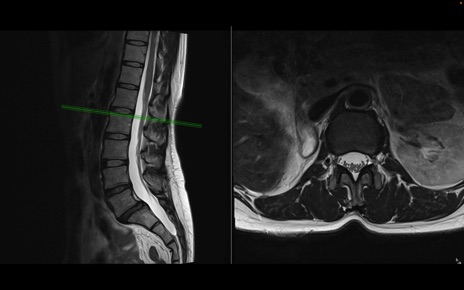

腰椎MRI

T2WI(横断像)

T2WI(矢状断像)